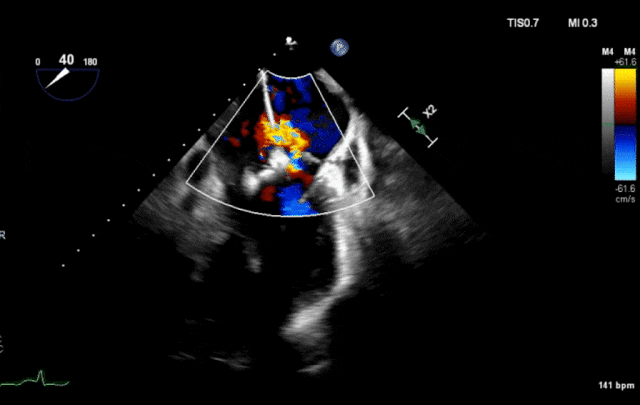

心脏超声示左室增大,二尖瓣2、3区脱垂伴重度反流(腱索断裂),Carpentier分型Ⅱ型,典型Barlow综合征表现;二尖瓣开放面积5.0cm²,3区瓣环内径31mm,前叶长22mm、后叶17mm,前叶收缩期关闭瓣体部分呈拱形突向左房腔,瓣膜游离缘对合欠佳,可见腱索断裂,长度9mm;2区瓣环内径32mm,前叶长22mm、后叶10mm,前后叶均可脱垂;三尖瓣重度反流。CDFI示瓣口重度偏心性反流,反流束沿主动脉后壁走行,肺静脉收缩期可见反向频谱。

术前反流

图片